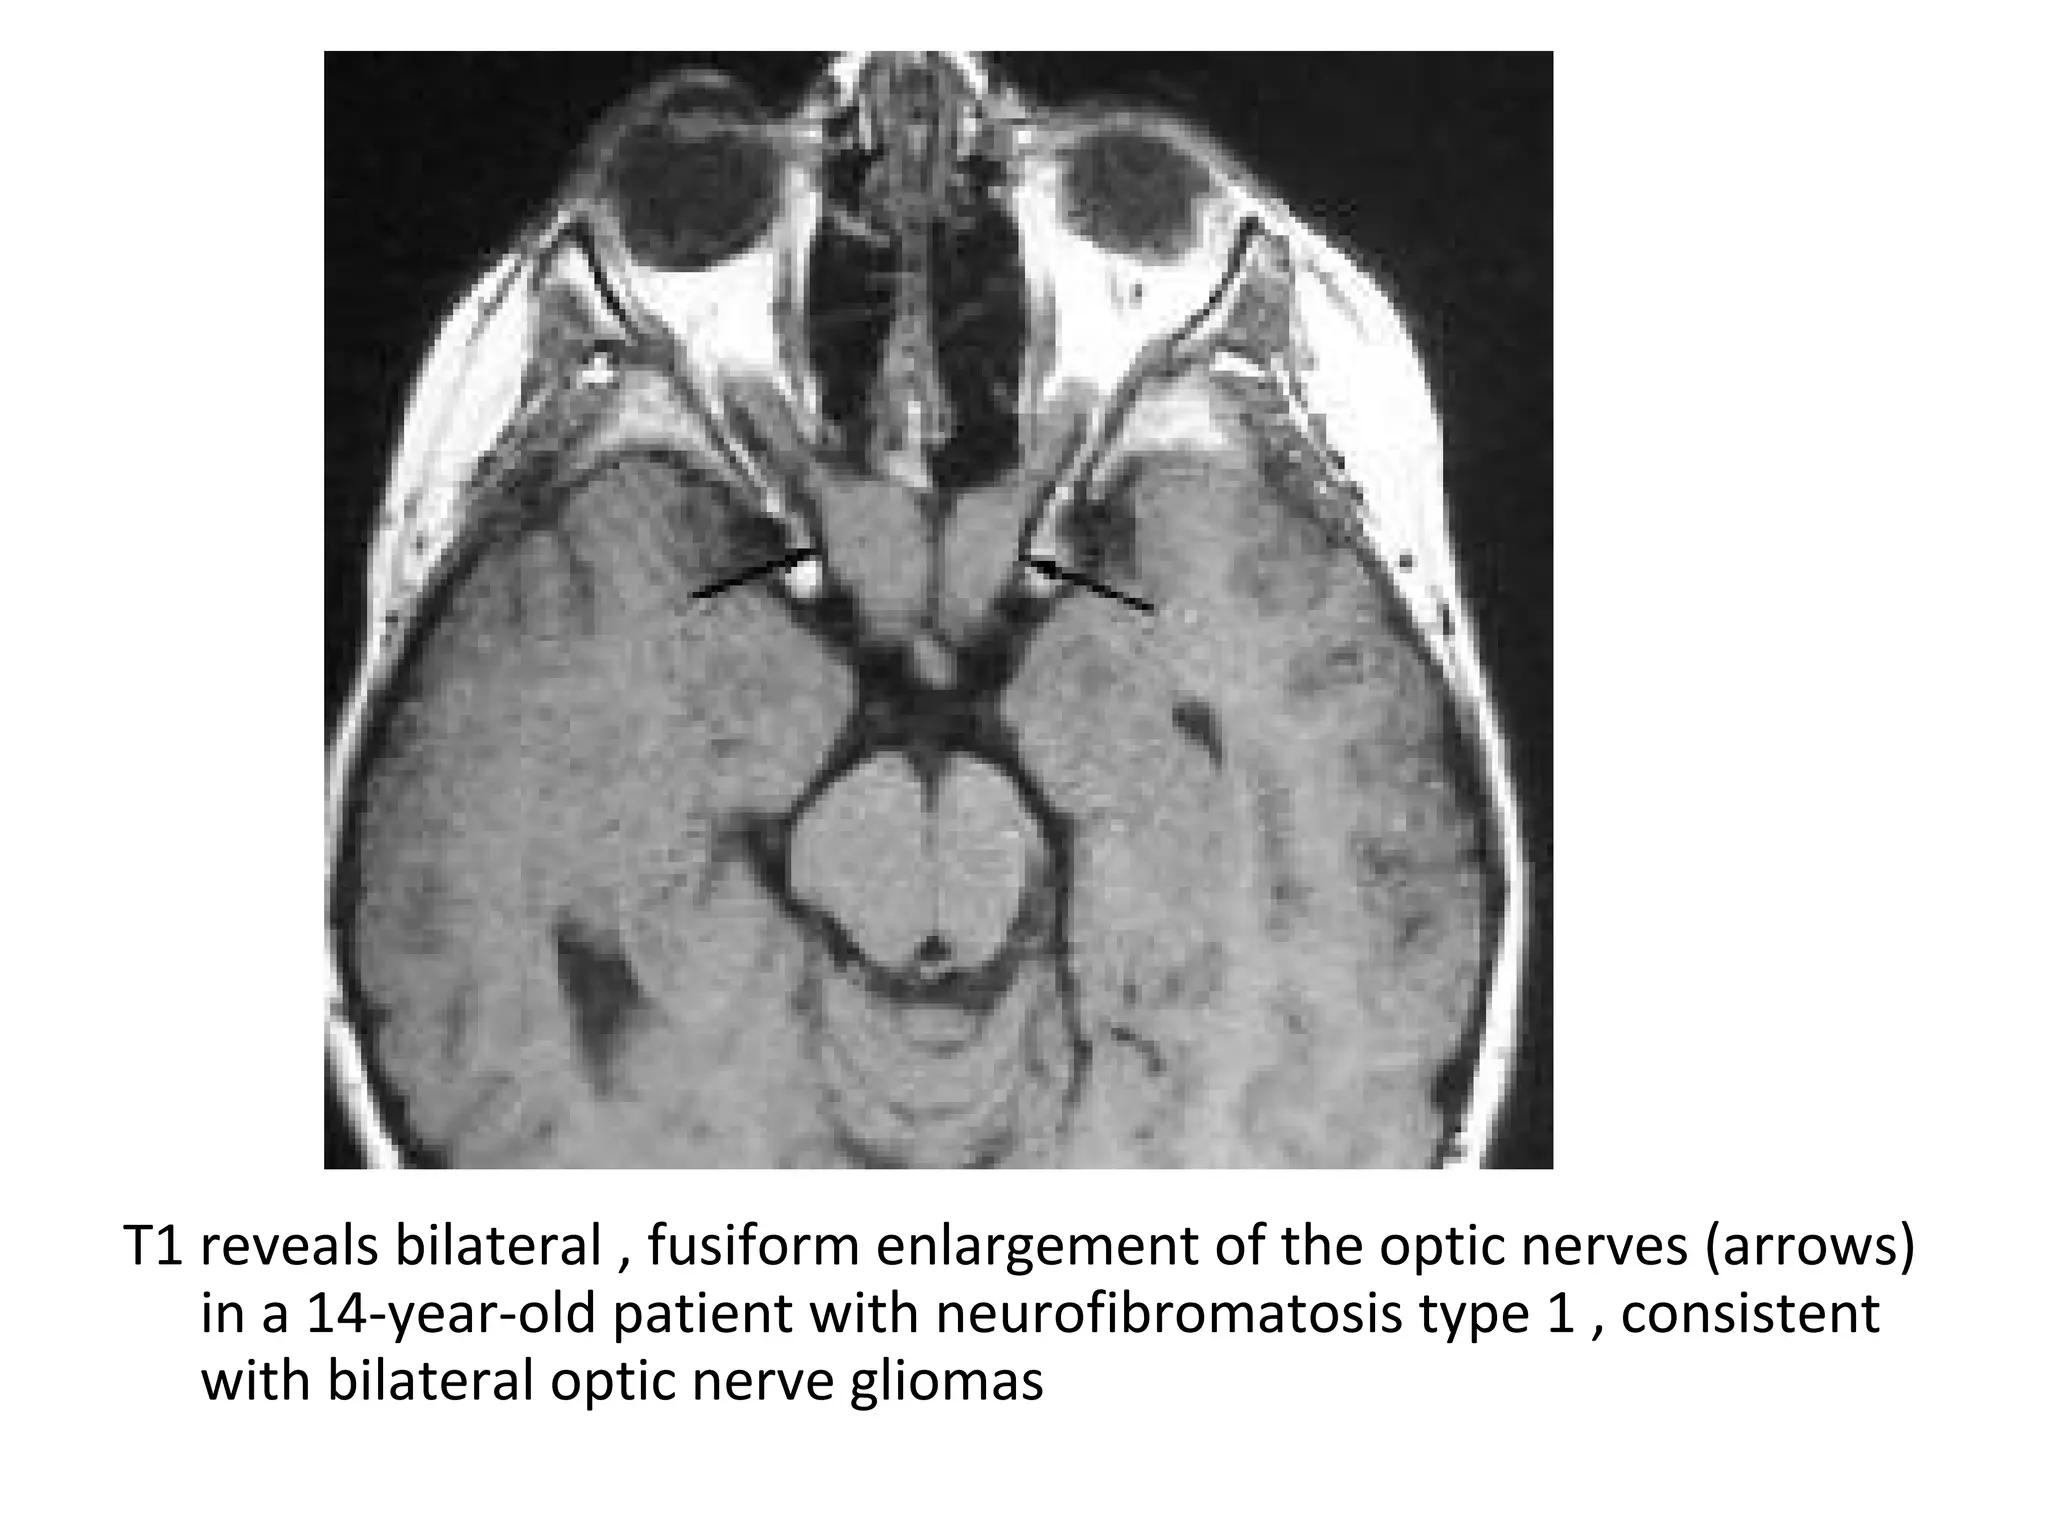

T1 reveals bilateral , fusiform enlargement of the optic nerves (arrows)

in a 14-year-old patient with neurofibromatosis type 1 , consistent

with bilateral optic nerve gliomas